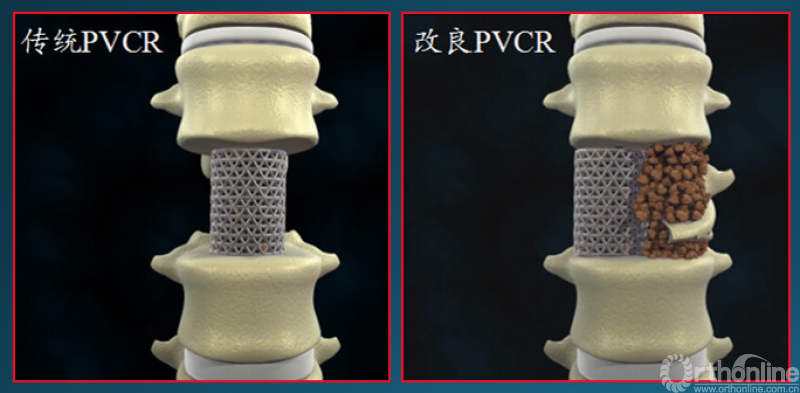

众所周知,脊椎结核后突畸形是结核病严重的后遗症之一。不仅影响患者外表仪容和心理,还可能出现晚发病灶造成截瘫。30多岁的小李就是一位脊柱结核后造成后凸畸形伴截瘫的患者,其畸形角度高达90度。针对此类患者的治疗大多就是截骨矫形,手术创伤大不说,椎体切除后造成的脊柱失稳等一系列后遗症也是令医生和患者担忧的。为解决临床上的这类问题,丁文元教授对传统的PVCR截骨技术进行了简化和改良,即后路单侧截骨部分椎体切除固定矫形术(UPVCR)入路,该技术采用后方单侧截骨,切除部分椎体、相邻椎间盘大部,保留对侧椎弓根及部分椎体,重建置入钛网支撑。随后,丁文元教授通过UPVCR技术对小李实施了手术,经过家人悉心地照顾,小李术后肌力恢复的良好,很快就出院了。三个月复查时竟是自己走路来的,临床疗效让患者及家人很是满意。

丁文元教授介绍说,UPVCR技术的优势在于手术操作简单,易于掌握,学习曲线短,手术时间短,出血少,神经并发症少;临床应用时极少发生断钉、断棒、不融合的现象,术中保留了良好的血运、植骨床,提供骨生长环境,保证部分骨支撑,术后极少发生矫正丢失,临床效果肯定。